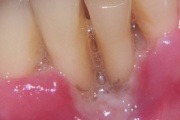

Igemed